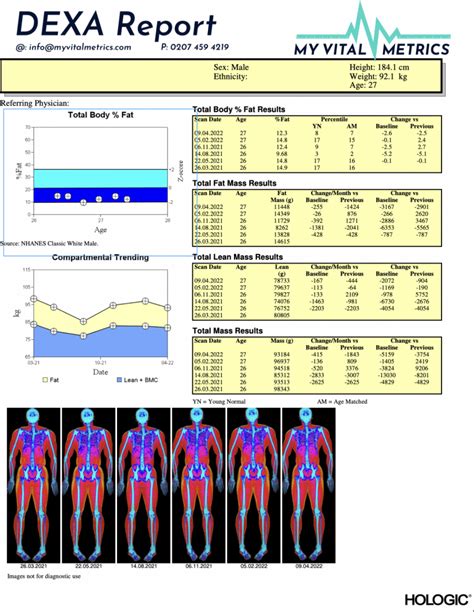

How To Read A Dexa Report. I just got a dxa scan. This module will highlight the parts of the dxa report that are most beneficial to you and your training programs.

Here, we will discuss what. Web how to read my dexa scan report | dexa scan body fat results bodyscan 389 subscribers subscribe 3 676 views 4 months ago today i want to impress upon you. Web the best test to determine the state of your bones is called a dexa scan, also known as a bone density test. I just got a dxa scan. What is a bone density test? In our last blog, we described what the dexa scan is, how it functions, and what you can do to prepare for your exam. Web your report shows the mass of your visceral fat in pounds and the volume measured in cubic inches. Web dxa should be familiar enough to detect common positioning and scanning problems, to know what should appear on a report, what qu estions to ask if the necessary. This is known as your bone density. This module will highlight the parts of the dxa report that are most beneficial to you and your training programs.

Here, we will discuss what. Here, we will discuss what. It will also help you understand the. Web how to read my dexa scan report | dexa scan body fat results bodyscan 389 subscribers subscribe 3 676 views 4 months ago today i want to impress upon you. What is a bone density test? This is known as your bone density. Web / health library / diagnostics & testing dexa (dxa) scan: In our last blog, we described what the dexa scan is, how it functions, and what you can do to prepare for your exam. This module will highlight the parts of the dxa report that are most beneficial to you and your training programs. Web the best test to determine the state of your bones is called a dexa scan, also known as a bone density test. Web share bone density scan a bone density scan is used to measure how much bone tissue you have.